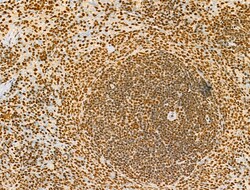

Invitrogen™ Phospho-AKT1 (Ser124) Polyclonal Antibody

Antibody detects endogenous levels of AKT1 only when phosphorylated at Ser124.

| Immunohistochemistry (Paraffin), Western Blot, Immunocytochemistry | |

| A synthesized peptide derived from human AKT1(Accession P31749), corresponding to amino acid residues around phosphorylated Ser124. | |

| Human, Mouse, Rat | |